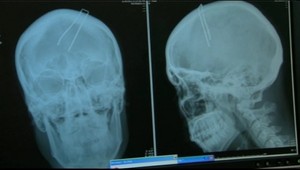

Obrovské nešťastie sa stalo v obci Sása v okrese Revúca. Muž, ktorý pílil drevený hranol nemal dostatočne pod kontrolou svoju pílu a tá spôsobila tragédiu. 15-ročnému chlapcovi sa zarezala do krku.

ostal len Jakub s Romanom. "Pri pílení dreveného hranola, ktorý poškodený držal na kláte obidvoma rukami, sa elektrická reťazová píla od hranola odrazila, pričom sa chlapcovi sčasti zarezala do krku. S ťažkými zraneniami ho vrtuľníkom previezli do nemocnice v Banskej Bystrici," uviedla hovorkyňa banskobystrických policajtov Mária Faltániová.

15-ročný Jakub asistoval susedovi, no a práve vtedy sa elektrická motorová píla od dreva odrazila a zarezala sa do Jakubovho krku. "Nepritlačil ju poriadne o klátik a mal veľmi blízko hlavu. Proste som si neskoro všimol, že zle držal tú dosku a vybehla mi spod rúk. Aj keď som ju okamžite vypol, ale už sa nedalo nič robiť,"